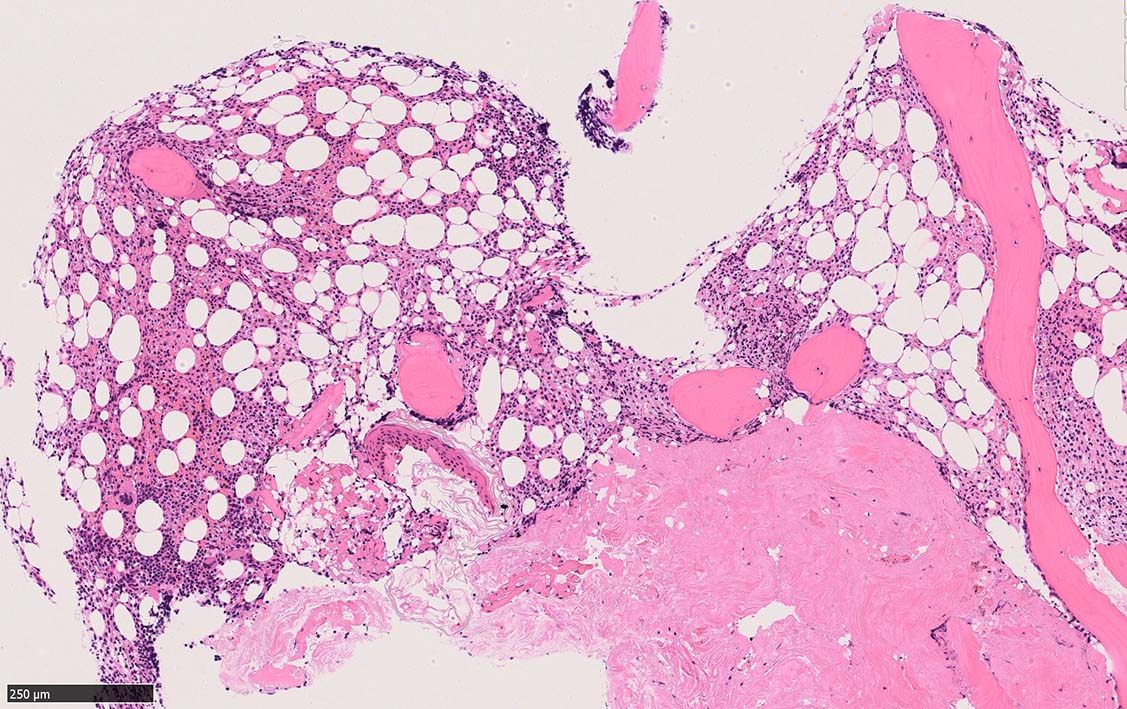

骨髄生検

bone marrow trephine biopsy: dry tapのため骨髄生検が行われる. cellularityは40-80%とhypercellular marrow. 流れのある細胞配列は線維化を疑わせる.

ASD-G 低倍率所見では赤芽球血島は幼若赤芽球の集簇巣が散在する, 顆粒球系細胞(ASDに赤く染色される)は減少,granulopoietic hypoplasiaを呈する.疎な集簇を示すmast cellsの増加がある.

ASD-G陰性の細胞がびまん性に増加しているように見える.

ASD-Giemsa陰性の細胞がシート状に増殖する. 核はクロマチン濃染, 核小体は不明瞭.類円形, 卵円形, くびれを持つ多稜形核, 長円形いびつで屈曲した核, など多彩. 細胞質は淡清色調, 広く淡明. 赤芽球血島は幼若赤芽球のみで形成される異形成像を示す. やや離れて成熟赤芽球が疎な集簇を示す.

Ag染色では, 疎な弾性線維が増生し,増殖細胞を小胞巣状に分画するいわゆる「lymphomatoid pattern」を呈する. 本例では, Mgkに異形成所見がある.